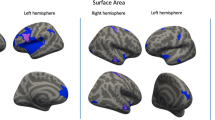

The first goal of this study was, therefore, to elucidate the relationship between autistic traits and a number of gray matter indices. First, we aimed to replicate our VBM findings from an earlier independent study (Geurts et al. 2013) (Table 1). Second, we aimed to extend these findings to associations in cortical thickness, surface area and structural coupling. Cortical thickness findings in ASD generally show atypical brain maturation (Raznahan et al. 2010), thinner cortical regions (Scheel et al. 2011; Wallace et al. 2010), and increased frontal lobe thickness has also been reported in adults with ASD (Ecker et al. 2013). In addition, positive associations between scores on the Autism Diagnostic Interview (ADI-R; Lord et al. 1994) and frontal and parietal thickness have been reported (Ecker et al. 2013). Based on these findings in ASD, we expected associations between autistic traits and cortical thickness in neurotypicals regardless of the direction. Reports on surface area (SA) in young adults measures have revealed reduced SA, primarily in orbito-frontal cortex and posterior cingulum (Ecker et al. 2013), or no differences between ASD and controls (Haar et al. 2014; Raznahan et al. 2010; Richter et al. 2015; Wallace et al. 2013). Here we didn’t expect SA differences to be related to autistic traits.

Whole-Brain Vertex-Wise Analyses

Vertex-wise GLM was performed to test the association between AQ-28-scores and cortical thickness, gray matter volume, and pial surface area. No significant associations were found between autistic traits and any of the gray matter indices in the Exploration sample. Similar to the DTI approach, we combined our samples resulting in N = 505 (three subjects were excluded in FreeSurfer analyses), and test the relationship between AQ-28-score and gray matter indices after controlling for multiple comparisons (FDR: p < 0.05). Again, no significant relationships were found with cortical thickness, gray matter volume and pial surface area.